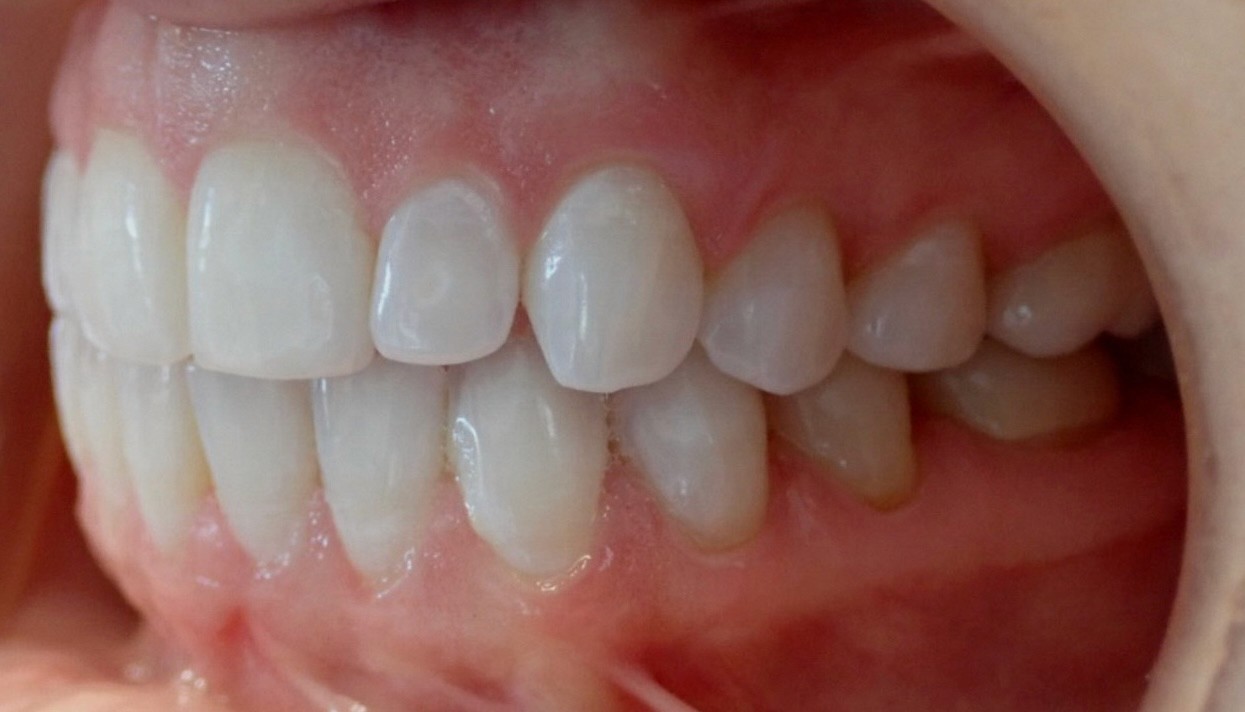

Final results

INTRAORAL